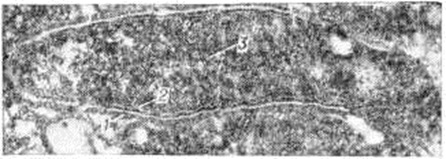

Электронно-микроскопическими исследованиями установлено, что ультраструктура возбудителя Лепра принципиально не отличается от строения других видов грамположительных бактерий. На поверхности микобактерий Лепра выявляется равномерный электроннопроницаемый (осмиофобный) слой толщиной 5—10 нанометров (наружный диффузный слой клеточной стенки). За ним следует осмиофильный слой клеточной стенки толщиной от 3 до 10 нанометров, состоящий из двух очень тонких некоторое, плотно прилегающих друг к другу. Непосредственно к внутренней поверхности клеточной стенки примыкает наружный слой цитоплазматической мембраны (рисунок 1), представляющей собой, как и у других бактерий, трёхслойную мембрану толщиной 7,5—9 нанометров. В бактериальной клетке встречаются 1—2 мезосомы с выраженным полиморфизмом (петлеобразные, везикулярные, трубчатые, пластинчатые, гроздевидные). В цитоплазме выявляется сравнительно небольшое количество рибосом, сферические электронно-плотные включения волютина диаметром 20—50 нанометров, включения, имеющие вид ограниченных мембраной вакуолей (предположительно липоиды), и гомогенные тельца, природа которых остаётся неизвестной. Ядро не имеет определённой формы, расположено в центре клетки вдоль её длинной оси, не ограничено мембраной. Иногда в лизирующихся под воздействием химиотерапии клетках микобактерий Лепра выявляются спороподобные образования (рисунок 2 и 3).

Рис. 1. | ||